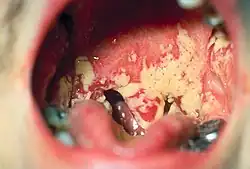

Pseudomembranous candidiasis in the mouth and oropharynx.

Pseudomembranous candidiasis in a person with HIV

Acute pseudomembranous candidiasis is a classic form of oral candidiasis,[6] commonly referred to as thrush.[4] Overall, this is the most common type of oral candidiasis,[7] accounting for about 35% of oral candidiasis cases.[8]

It is characterized by a coating or individual patches of pseudomembranous white slough that can be easily wiped away to reveal erythematous (reddened), and sometimes minimally bleeding, mucosa beneath.[7] These areas of pseudomembrane are sometimes described as "curdled milk",[4] or "cottage cheese".[7] The white material is made up of debris, fibrin, and desquamated epithelium that has been invaded by yeast cells and hyphae that invade to the depth of the stratum spinosum.[4] As an erythematous surface is revealed beneath the pseudomembranes, some consider pseudomembranous candidiasis and erythematous candidiasis stages of the same entity.[4] Some sources state that if there is bleeding when the pseudomembrane is removed, then the mucosa has likely been affected by an underlying process such as lichen planus or chemotherapy.[5] Pseudomembraneous candidiasis can involve any part of the mouth, but usually it appears on the tongue, buccal mucosae or palate.[7]